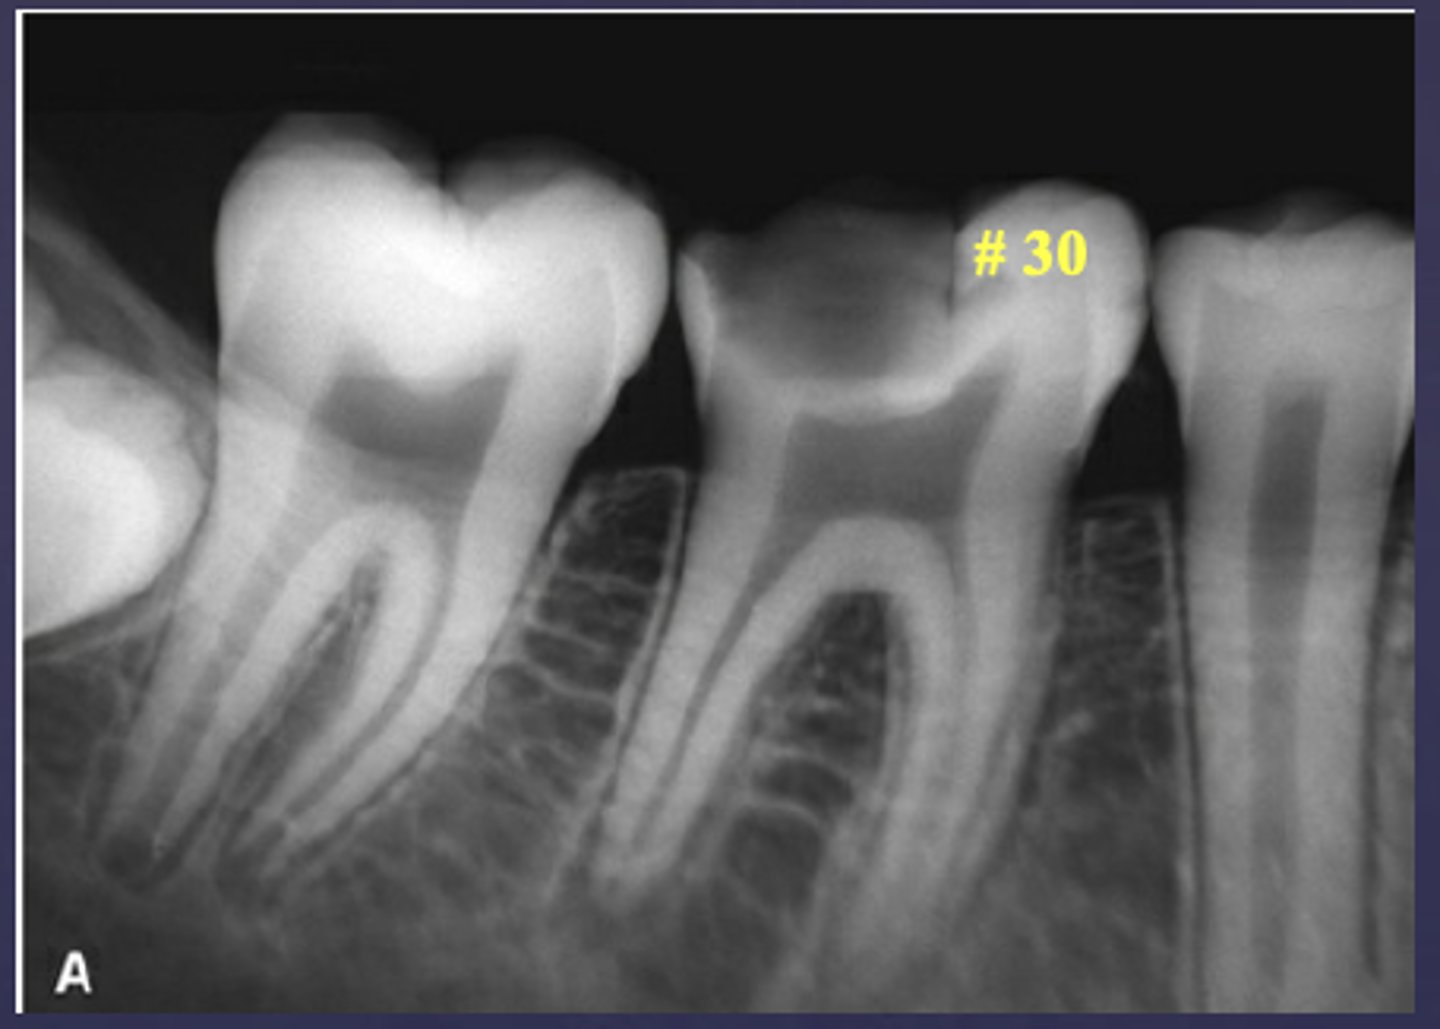

What type of change is seen in this radiograph?

early change (apical periodontitis #14)